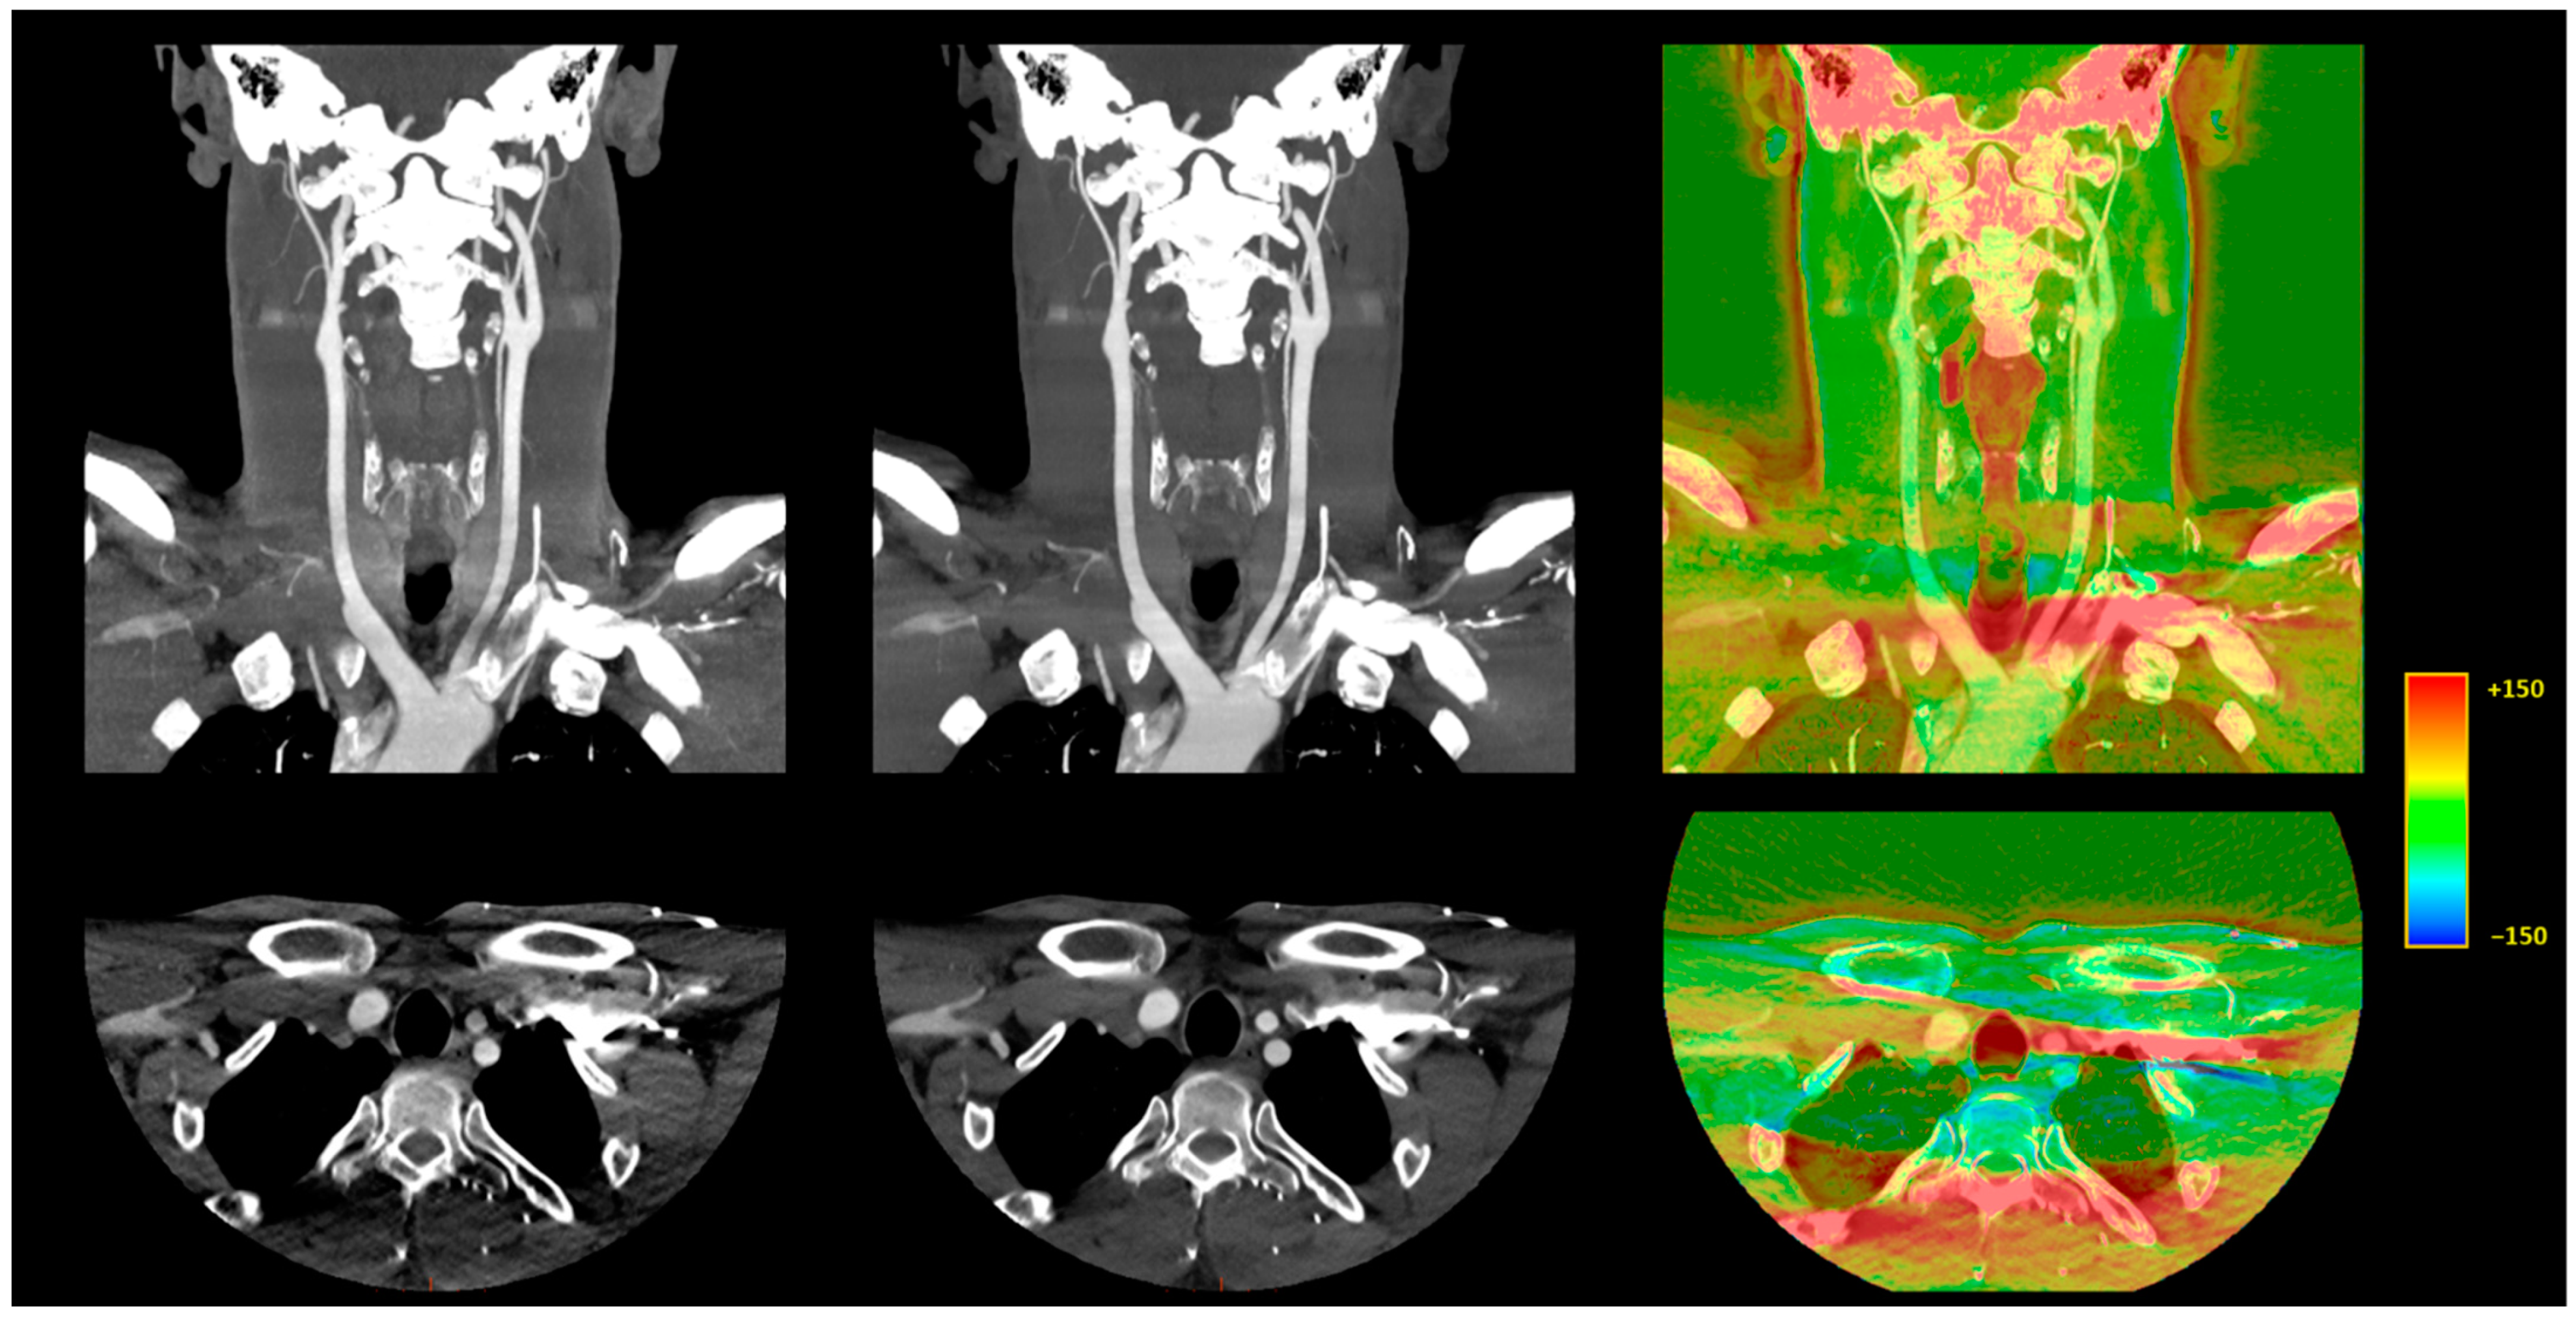

3.3.1. Image Signal Fluctuation with DLR vs. H-IR

3.3.2. Comparison of the Two Reconstruction Techniques at Constant kVp Value

3.3.3. Comparison of Low kVp plus DLR vs. Standard kVp plus DLR

3.3.4. Comparison of Low kVp plus DLR vs. Standard kVp plus H-IR

3.4. Qualitative Image Analysis